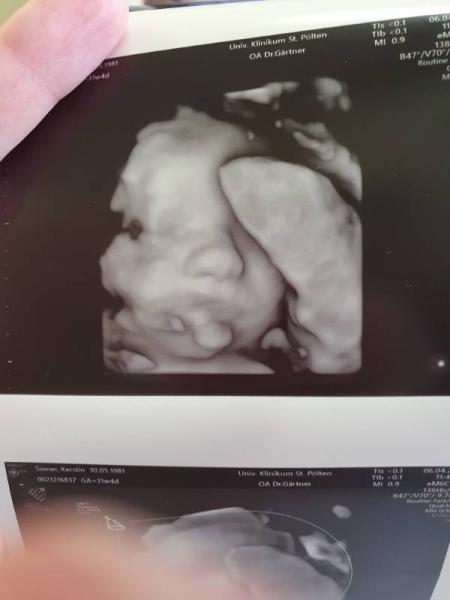

Hallo Mädls, Hab ein witziges Bild für euch. Meine Maus liegt leider etwas hinter der Nabelschnur und den Mund sieht man leider nicht so gut, weil sie an der Nabelschnur nuckelt GlG Kerstin

Bild zu Baby nuckelt an Nabelschnur - Forum für Juni - Mamis